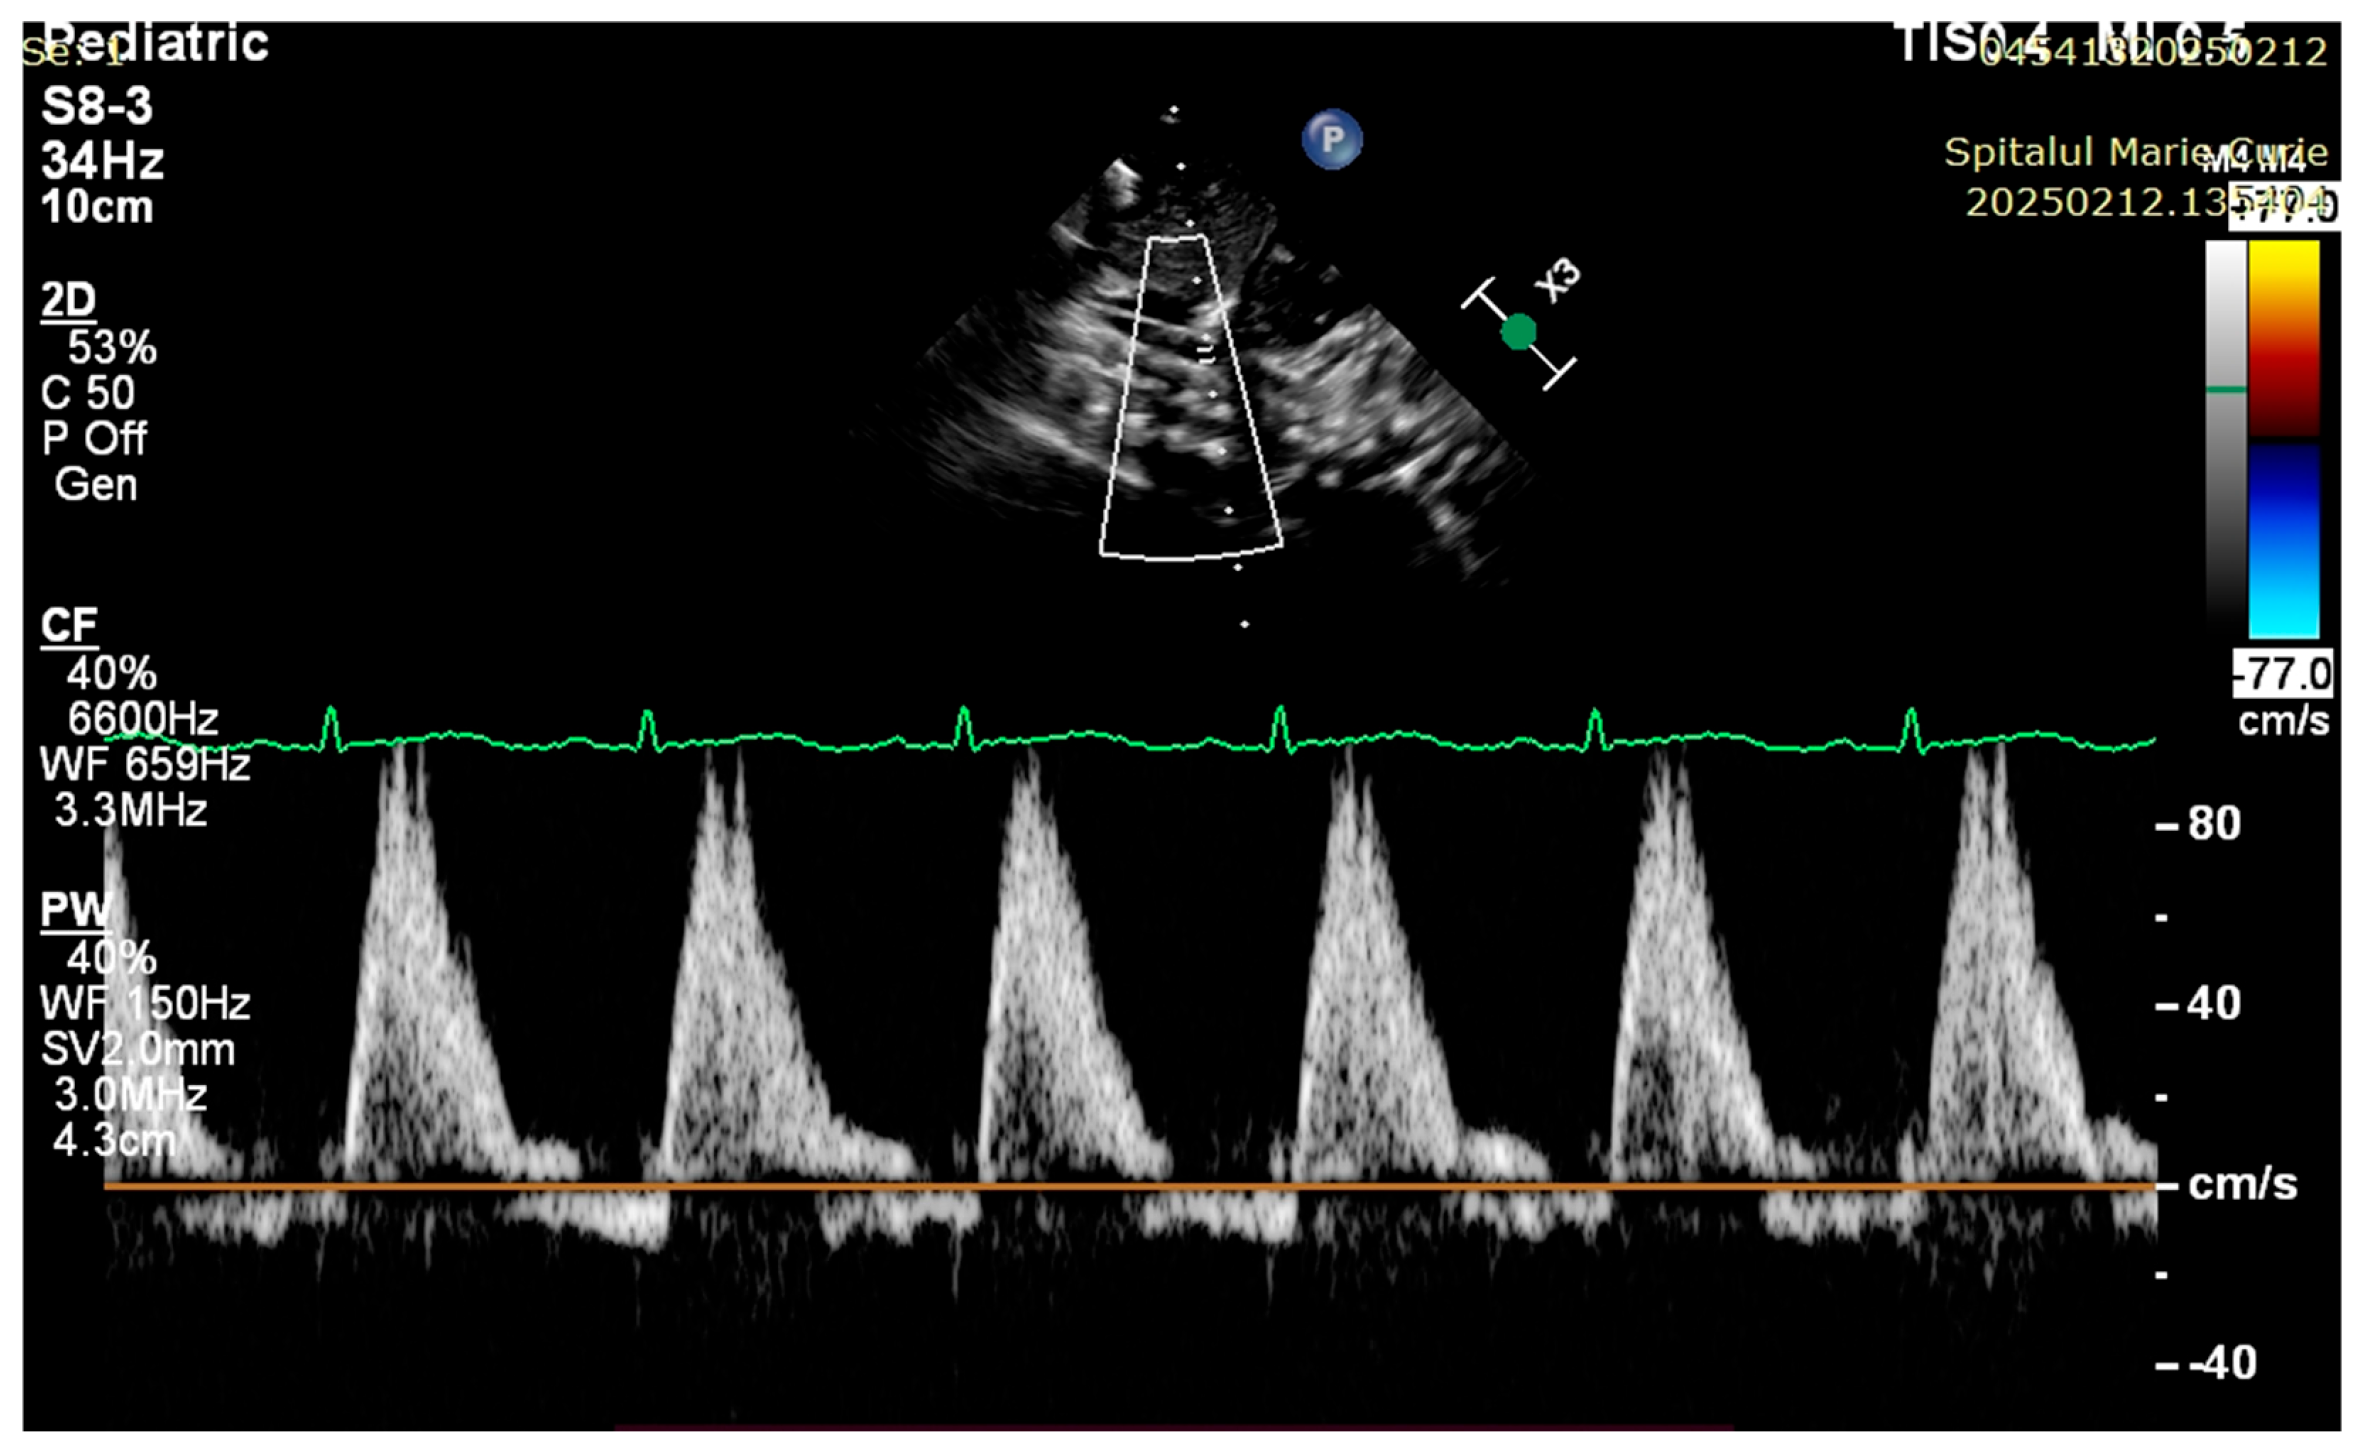

4. Case Reports